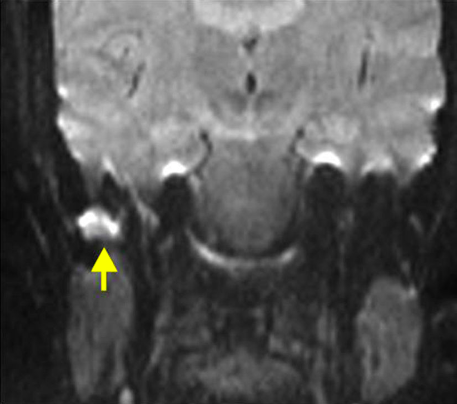

Hallazgos de T2 en mastoiditis complicada:

• Señal aumentada

• Disminución de señal en seno sigmoideo

• Capta contraste